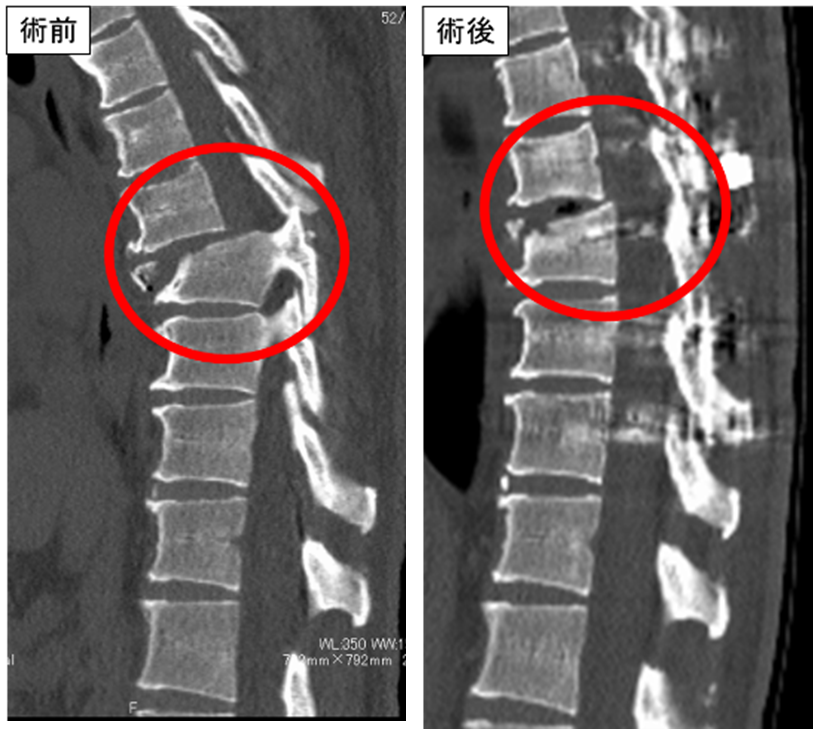

胸椎脱臼骨折を認めますが、両下肢筋力低下がなかったため、体位変換や術中操作による脊髄損傷が危惧されましたが、術中脊髄モニタリングを駆使し慎重に手術を行いました。

術後麻痺なく独歩可能です。

頚椎脱臼骨折を認めるが、四肢の筋力低下

は認めなかった。術中脊髄モニタリングを駆使し

慎重に手術を行いました。術後麻痺なく独歩可能です。